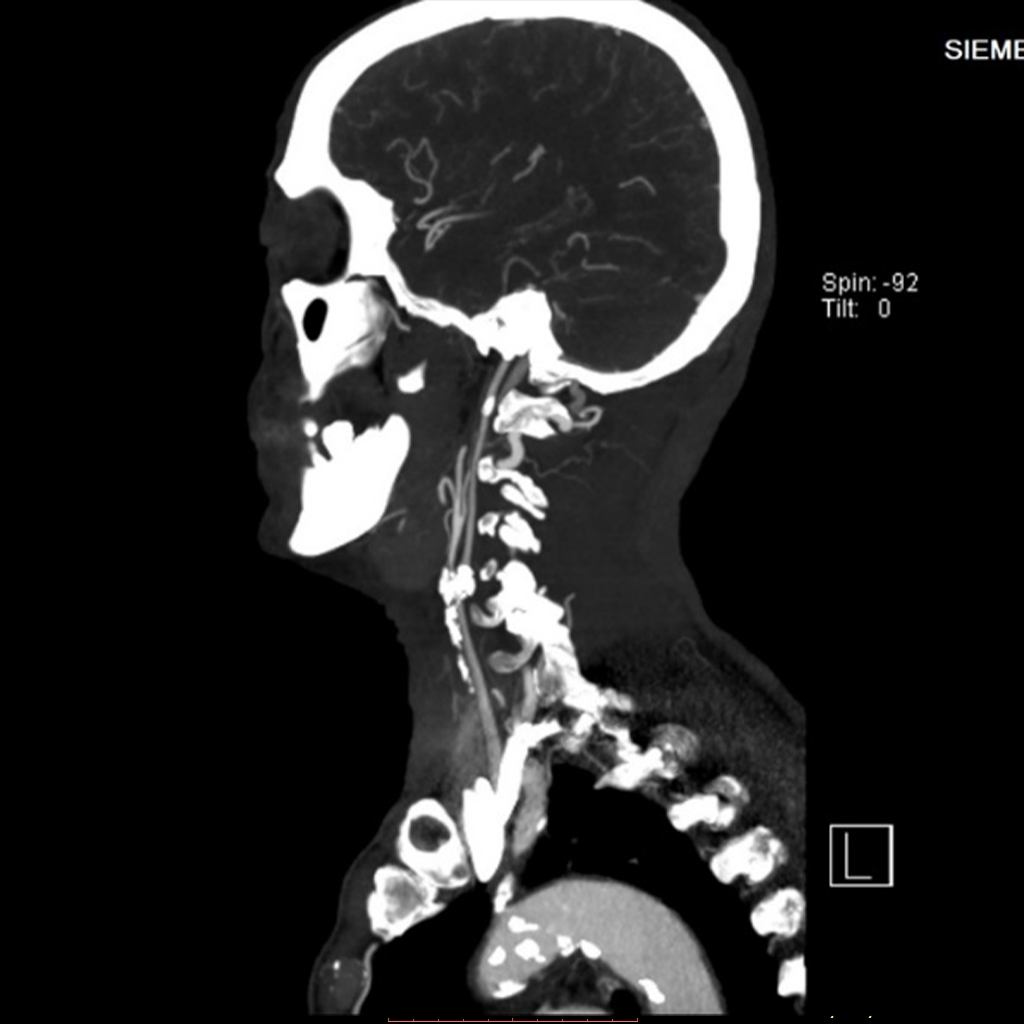

▲术前CTA检查见患者主动脉弓、颈动脉多处粥样硬化斑块,左颈总动脉分叉处血管重度狭窄

考虑到患者近来出现短暂性脑缺血发作(TIA),为避免严重脑卒中、脑缺血事件发生,在药物治疗的基础之上,需及时手术干预。

经血管外科科内讨论,该患者病情进展快,症状重,颈动脉粥样硬化斑块性质不稳定,同时考虑到患者年龄及身体状况,决定为该患者实施颈动脉内膜剥脱术。